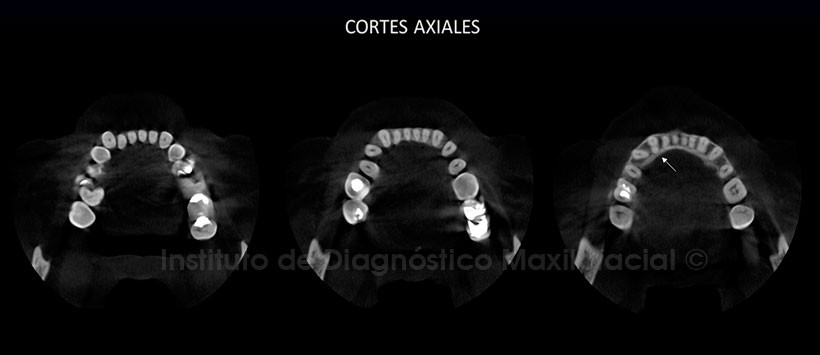

Sin embargo en la reformación panorámica obtenida mediante la tomográfica volumétrica de haz cónico (Figura 2), encontramos que la pieza 43 presenta una variante anatómica a nivel radicular la cual se pudo confirmar en las vistas axiales (Figura 3).

En el corte transaxiales y tangenciales (Figura 4), se pudo determinar que la pieza 43 cuenta con una raíz en sentido vestibular y otra en sentido lingual, así mismo se pudo evidenciar que cada segmento radicular cuenta con un conducto propio de manera independiente.